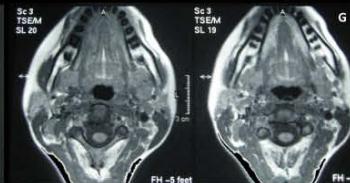

Figure/Patient 2

A case of right mandibular lymphangioma in a 10 year-old boy, hypoechoic with some septations and no blood vessels (A) and hyper-intense on T2 axial (B) and coronal (C) MR scans.